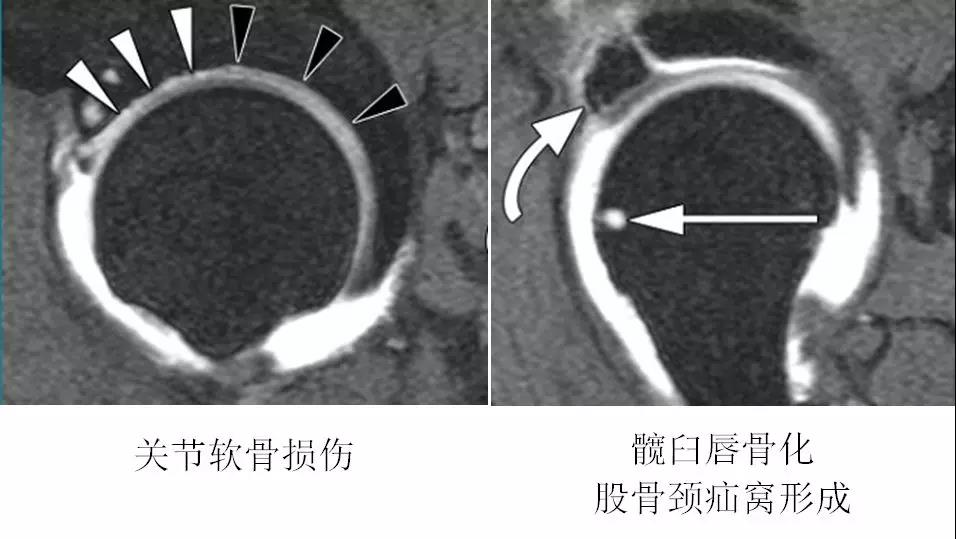

MRI表现

- 基本表现同X线。

- 对髋臼盂唇和软骨损伤的检出有较高的敏感性和特异性。

- 其它表现:

- 股骨颈疝窝

- 关节积液及滑膜增生

- 骨髓水肿MR造影优于常规MR

- 股骨头颈联合处前上缘骨性突起。

- 凸轮撞击型FAI--并盂唇撕裂。